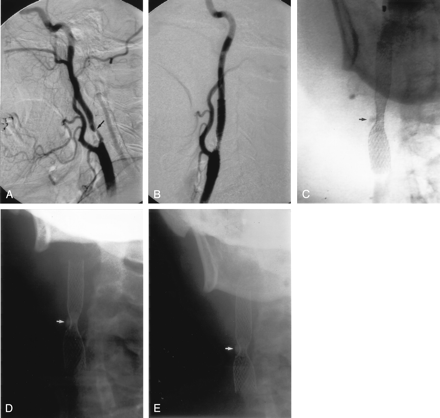

Immediate poststent angiography showed a moderate improvement in the degree of stenosis in most patients. In some patients, the improvement was dramatic, with one stenosis decreasing from 99% to 29% (Fig 1). In most patients, however, the improvement was more gradual (Fig 2). On average, the angiographic stenosis improved from 83% to 49% immediately after stent placement (median, 48%; range, 29–73%). Two patients still had stenosis in the severe range (>70%); the worst of these was 73%. Both improved by 2–3 months to 18% and 20% residual stenosis, respectively. At last follow-up in all patients the mean residual stent stenosis was 19% (median, 16%; range, 0–54%). Comparing matched pairs of measurements in the same patients over several time intervals, the maximum stent expansion occurred during the procedure, followed by a gradual further expansion over the next 4–12 months (Fig 3). After the first year, the appearance remained stable out to 44 months.

A, Left CCA DSA, AP view, showing a severe stenosis of the proximal ICA, measuring approximately 76% (arrow).

B, Repeat DSA, AP view, immediately poststenting without balloon angioplasty, showing reduction of the stenosis to approximately 50% (arrow).

C, Follow-up DSA, AP view, 3 years poststenting alone, shows no residual ICA stenosis.

D, E, and F, Conventional AP radiographs of the neck immediately poststenting (D), 1 month (E) and 8 months (F) poststenting, showing progressive opening of the stent waist (arrow), with maximum expansion occurring in the 1st month postprocedure.